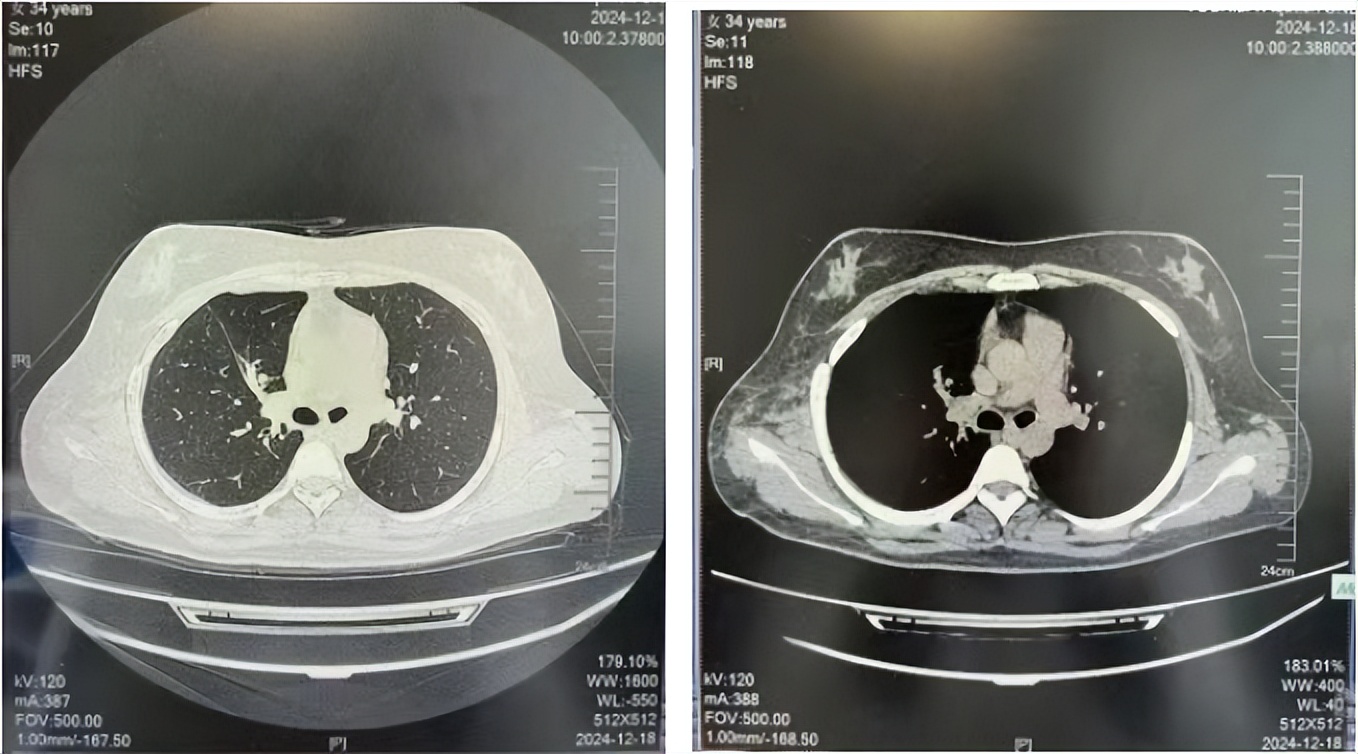

2016年1月复查CT提示支气管截断可见新发小结节,一线治疗采用培美曲塞+DDP方案化疗4周期(培美曲塞3.36,DDP 480mg)。化疗后复查胸部CT:右肺见不规则结节样影,最大层面大小约19mm*8mm,较前比较明显增大,疗效评估PD。2017.3-2017.4予单药多西他赛化疗3周期,疗效评估SD。2018年5月末复查CT提示结节较前增大,评效为PD,2018年6-10月予多西他赛+CBP化疗4周期,疗效评估SD。2022年5月患者出现活动后气短,复查胸部CT示右肺膨胀不良;右侧胸腔积液增多。胸腔积液包埋病理示符合肺腺癌细胞。行NGS基因检测:EML4:exon13-ALK:exon20融合。PD-L1(克隆号22C3)TPS<1%。

2018.07

2024.12